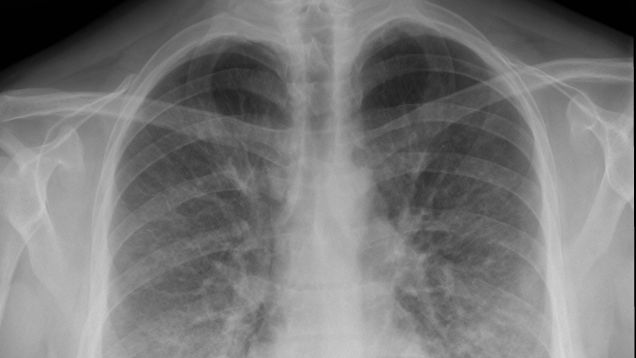

In a new report out Monday, health officials from the Centers for Disease Control and Prevention (CDC) have acknowledged that the wave of lung illness cases and deaths linked to vaping has a main bad guy: Products that contain THC sold on the black market. But to the disappointment of some experts, the agency is still…